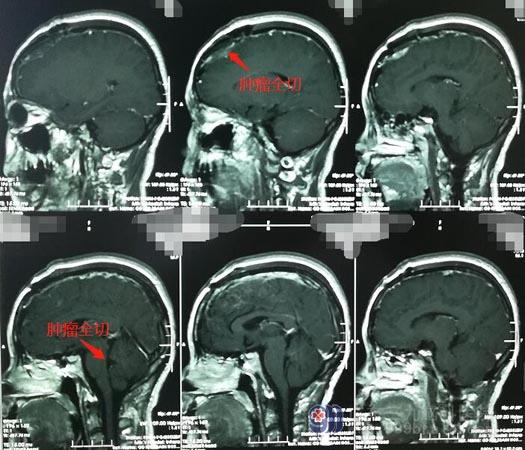

2019年10月份,医院副院长、神经外五科主任鲁明带领团队为赵女士施行了“右侧桥小脑角区听神经鞘瘤切除术”。术后,赵女士没有任何并发症出现,很快便康复出院。

今年5月份,赵女士再次来到神经外五科。她说第一次手术非常成功,所以对第二次的手术充满了信心。鲁明说,这次手术虽然比第一次相对简单一些,可毕竟几个月前才刚刚经历一次复杂的开颅手术,身体状况不比正常人,手术仍有一定的风险;但也不能再等待太久时间,肿瘤也会越来越大的。完善相关术前准备后,赵女士进行了第二次手术,手术很顺利。术后,赵女士四肢活动正常,身体状况也一天比一天好了。